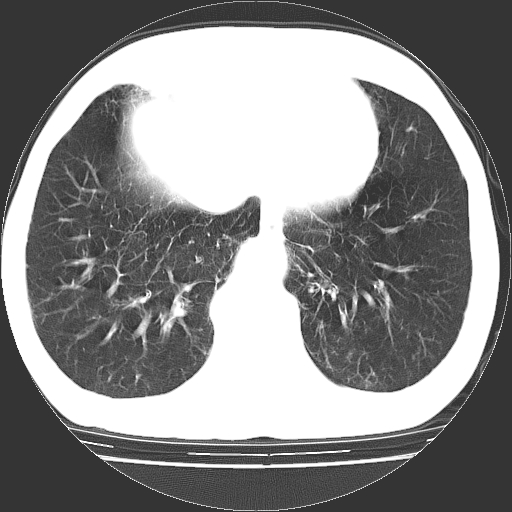

以下是引用hhcckk在2009-1-1 15:38:00的发言:[br]左下肺少许絮状模糊影--考虑感染[br]两肺散在小点状密度增高影--结合病史考虑矽肺?[br]气管壁钙化--可能由于老年退变性引起的